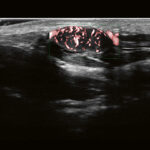

Ultraširokopojasne sonde kod Aplio i-serije pokrivaju isti raspon kao i dvije konvencionalne sonde, pružajući vrhunsku osjetljivost i rezoluciju za blisko i daleko polje. Iako pomaže u smanjenju troškova, ovaj revolucionarni dizajn sonde može pružiti bolju sliku bez obzira na stanje pacijenta.

Izuzetan detalj za precizniju dijagnozu